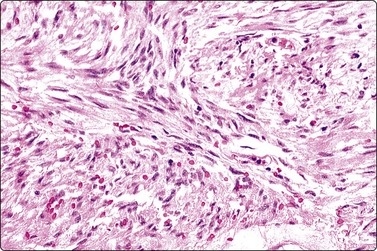

Gastrointestinal stromal tumors (GISTs), formerly classified as smooth muscle tumors, have now been extracted as a distinct entity. They are mesenchymal tumors, arising in the wall of the gastrointestinal tract, showing a spectrum of benign, borderline and malignant behavior. They are typically spindled but there is also an epithelioid variant showing the same antigen profile. Cytodiagnosis of the spindle-celled variant is relatively simple, showing fascicles of spindled cells with elongated, cigar- or comma-shaped nuclei, often set in a wispy filamentous background (Fig. 11.22A and B). The epithelioid variant presents greater difficulty, resembling epithelial tumors. The cells are round, cytoplasm distinct with a perinuclear halo, and nuclei vesicular (Fig. 11.22C). The tumors express CD117 (C-kit) and CD34 (Figs 11.23 and 11.24), but are negative for desmin, S-100 and keratin. Cytopathologists must be ‘GIST-conscious’ owing to the responsiveness of these tumors to Gleevec, which can induce tumor regression and long-term response, even in metastases.132-136

image image

Fig. 11.22 Gastrointestinal stromal tumor (GIST)

(A, B) Spindle cell variant; typical pattern (A, Pap, LP; B, MGG, IP); (C) Epithelioid variant (MGG, HP).